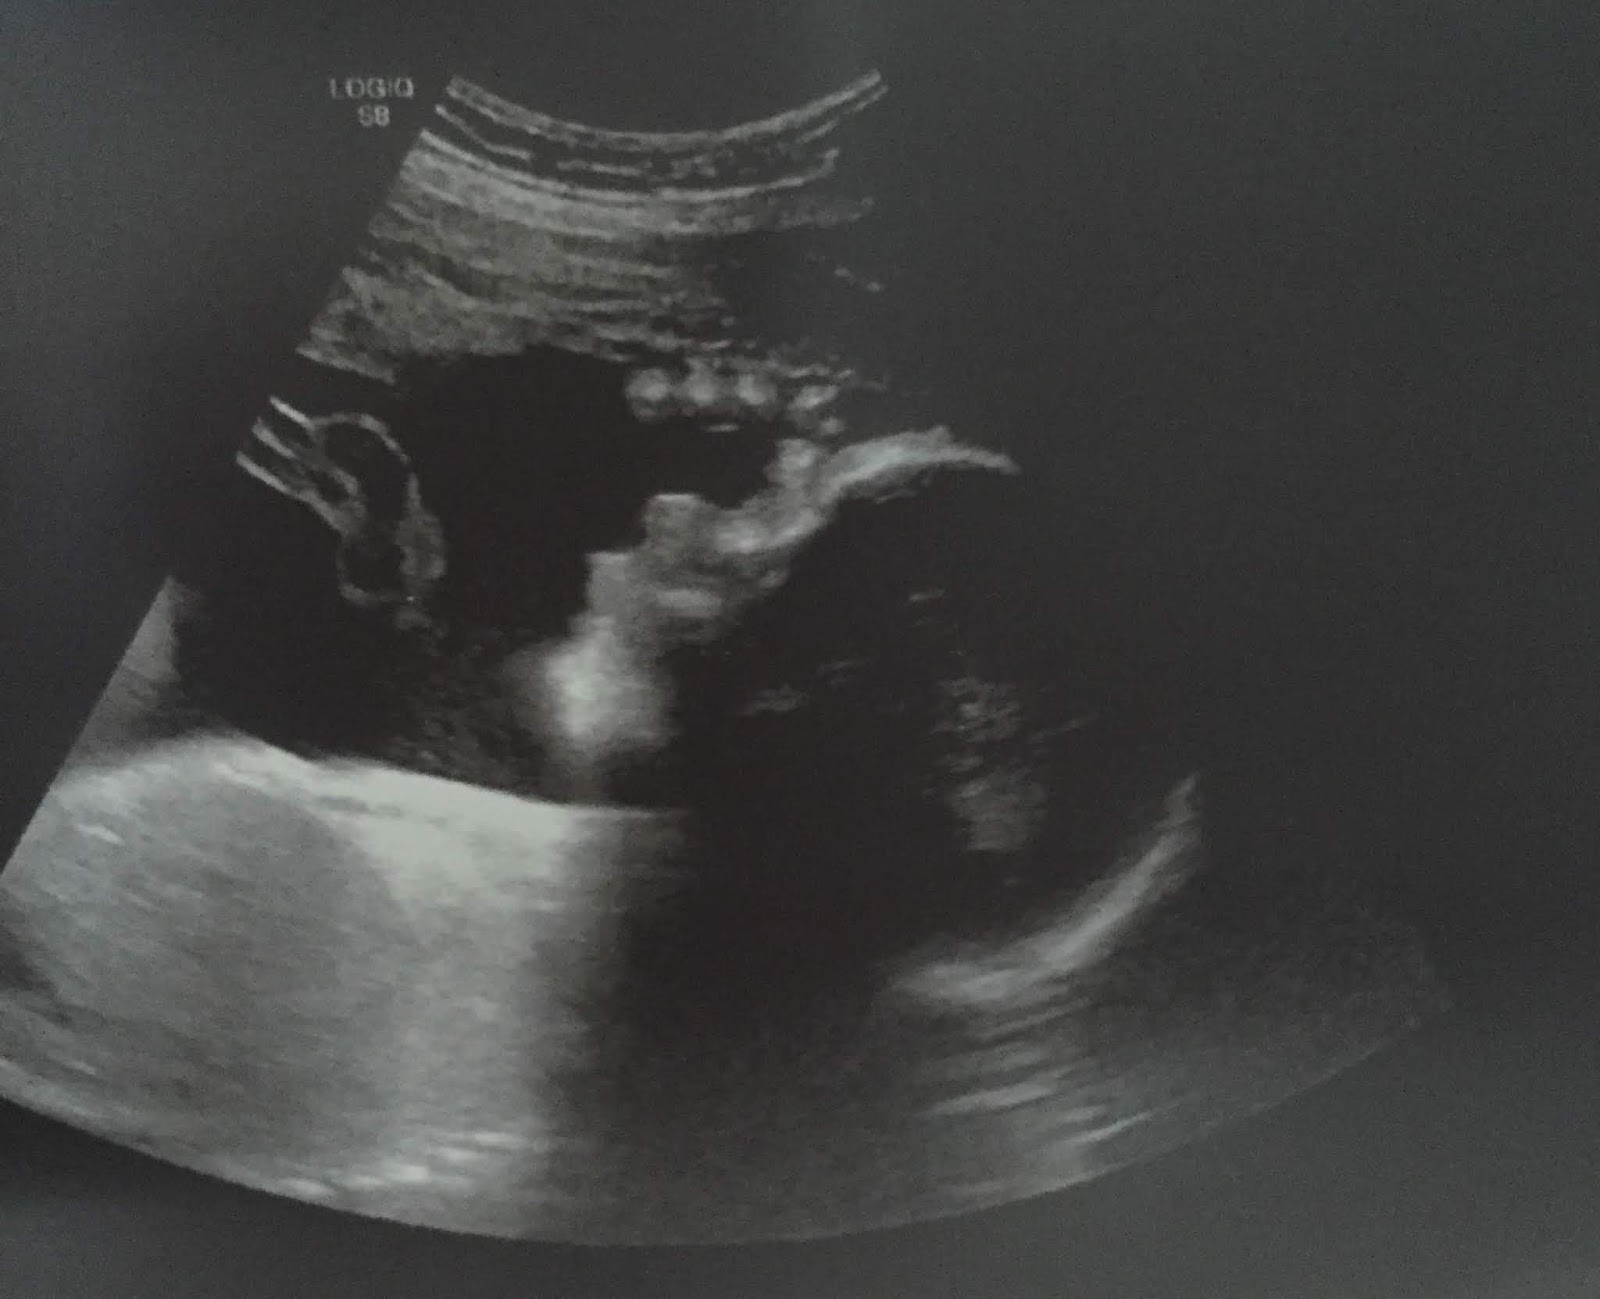

Baby Chris is 20 Weeks Old

20 weeks after fertilization (22 weeks LMP), Baby Chris is 11 inches long and weighs 15 ounces; he or she is the size of a spaghetti squash. Baby Chris’s cochlea is now fully developed, allowing him or her to hear the mother’s heartbeat and other sounds.